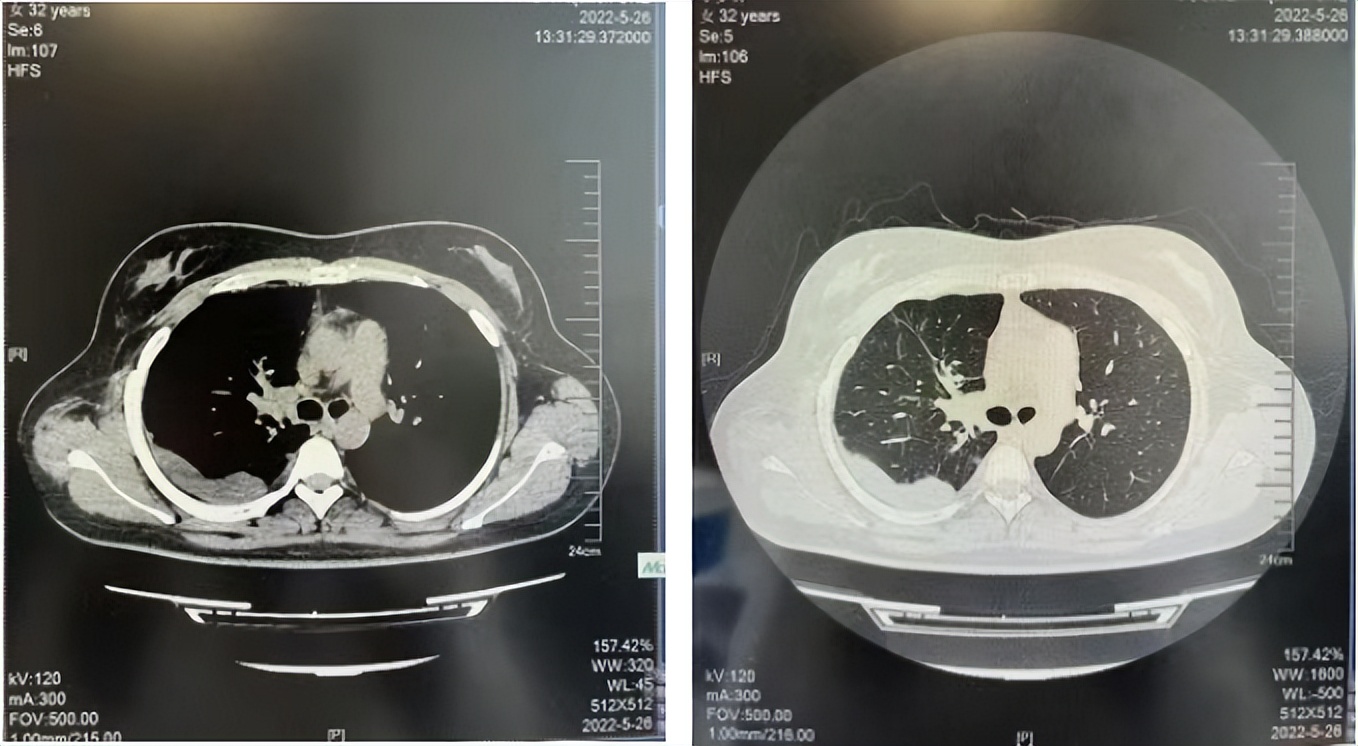

2016年1月复查CT提示支气管截断可见新发小结节,一线治疗采用培美曲塞+DDP方案化疗4周期(培美曲塞3.36,DDP 480mg)。化疗后复查胸部CT:右肺见不规则结节样影,最大层面大小约19mm*8mm,较前比较明显增大,疗效评估PD。2017.3-2017.4予单药多西他赛化疗3周期,疗效评估SD。2018年5月末复查CT提示结节较前增大,评效为PD,2018年6-10月予多西他赛+CBP化疗4周期,疗效评估SD。2022年5月患者出现活动后气短,复查胸部CT示右肺膨胀不良;右侧胸腔积液增多。胸腔积液包埋病理示符合肺腺癌细胞。行NGS基因检测:EML4:exon13-ALK:exon20融合。PD-L1(克隆号22C3)TPS<1%。

临床诊断:右肺上叶恶性肿瘤rT0N0M1a IVA期(第9版分期);恶性胸腔积液。

诊疗经过:2022年5月始口服克唑替尼3个月,出现肝功能异常(DILI 2级伴临床症状),改用恩沙替尼靶向治疗至今,目前评效为维持PR。恩沙替尼应用期间出现轻度肝功能异常(DILI 1级),对症处理后好转。截止目前PFS 33个月。

2018.07

2022.05

2022.08

2023.05

2024.12